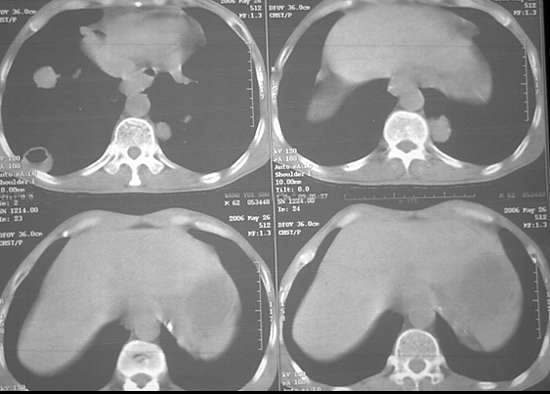

男62肺癌治疗后复查

具体治疗措施不清楚,治疗前空洞很少,请讨论空洞的性质

双肺内及胸壁旁见有多发软组织实性阴影和空洞,实性病变多见有脐凹切迹,贴近胸膜的见有胸膜凹陷征;空洞的壁多为厚薄不均,形态不规则,纵隔内见有较多肿大淋巴结,诊断为双肺内转移性病变。

双肺内及胸壁旁见有多发软组织实性阴影和空洞,实性病变多见有脐凹切迹,贴近胸膜的见有胸膜凹陷征;空洞的壁多为厚薄不均,形态不规则,纵隔内见有较多肿大淋巴结,诊断为双肺内转移性病变。[气囊或孔洞实为腺癌缘肺泡壁生长所致]

由于各叶cpm灶发生率之间并无显著性差异,故可认为cpm发生与其所在部位无关。对空洞形成有何临床意义尚无统一认识,有人认为是瘤灶消散时的表现,亦有人认为空洞代表病情恶化[6,7】。本组空洞缩小或增大、消失或出现并不与病情好转或恶化保持一致,说明有无空洞或空洞大小并不反映病情变化,其临床意义不大,而瘤灶的数目及大小,特别是瘤灶实性成分的多少才可能更准确反映病情变化。

单个cpm灶的空洞形态具有多样性,壁可薄可厚,厚度可均匀可不均匀,瘤灶大小变化也大。但总的说来,cpm 的洞壁较薄,4mm以下者最多(53%),其次为4—15mm者(34%),而15mm以上者却较少。另外洞壁厚度均匀者也较多(47%)。笔者认为这些与壁薄而均匀的囊样及小环形空洞较多有关。一般认为壁薄而均匀者多为良性空洞,而癌性空洞的壁多较厚或厚薄不均。woodring等-8 j认为洞壁厚度4mm以下者92%为良性,15mm 以上者95%为恶性,15mm者良恶性各半。蒋瑾等-9 j发现83% 的原发空洞型肺癌的壁厚度超过15mm。以上说明cpm的空洞形态不同于肺良性空洞及原发癌性空洞,具有其独特性。本组40%(16/40)的病例中同时存在多种空洞,说明cpm病例具有空洞类型的混合性。同样的洞腔变化既可见于病情好转时,也可见于病情恶化时,特别是同一种病例可同时出现两种相反的洞腔变化,说明洞腔变化具有非恒定性。

右肺门软组织块影,右主支气管及中间段支气管管壁明显增厚,两肺内多发结节及大小不等的类圆形薄壁空洞,纵隔内多发肿大的淋巴结;

考虑:1.右中央型肺癌伴两肺广泛性转移及纵隔转移。